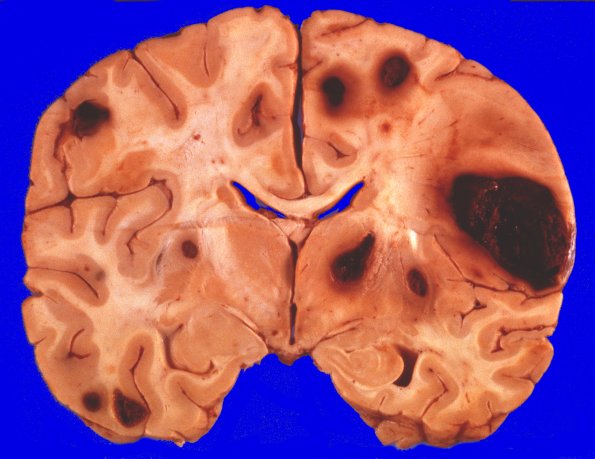

NEOPLASMS (METASTASES)

Melanoma

Metastatic melanoma, no further history on this case. (Thanks Tom Ulbright, MD)